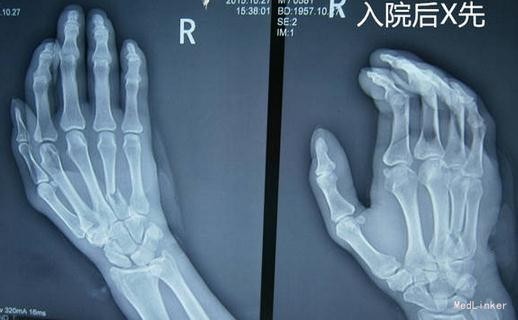

患者58岁,男性。于2015-10-25在工地上外伤致第4掌骨开放性骨折,在当地诊所给予缝合术,2天后因肿胀严重,来我院拍片,因位置不好,收住入院。

第4掌骨开放性骨折,肿胀严重